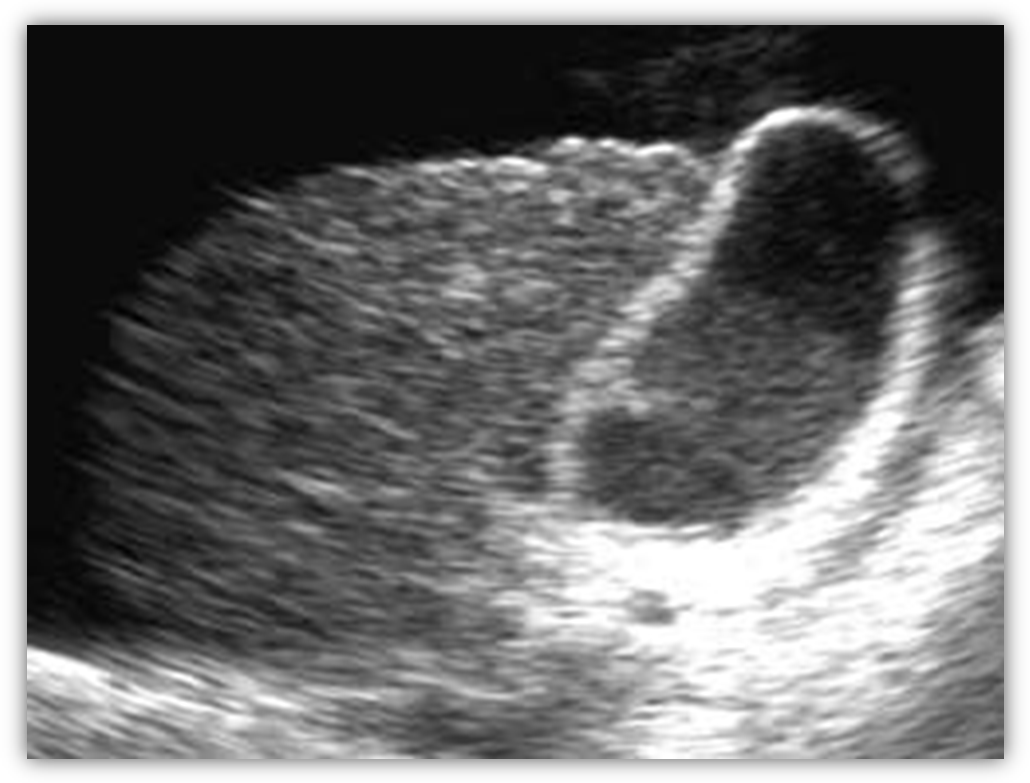

1. УЗД печінки

Цироз печінки можливо діагностувати на основі дослідження в режимі «сірої шкали» при візуалізації печінки з неоднорідною структурою паренхіми і нерівним бугристим контуром.